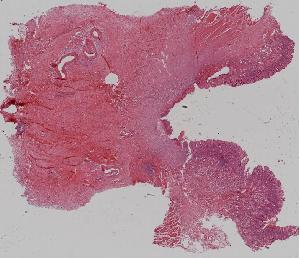

8.肉芽组织